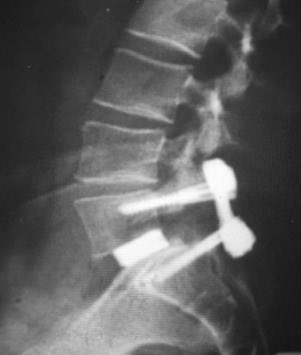

علاج هذه الحالات يبدأ بالعلاج الطبيعي والذي قد يحسن من اعراض المريض لكن لا يغير في درجة الانزلاق. ويجب الاستمرار على التمارين والا الاعراض تكرر بعد تركها. الجراحة هي الحل الآخر والذي يتضمن التوسعة على الاعصاب وتثبيت الفقرتين بدعامة، مسامير واسياخ